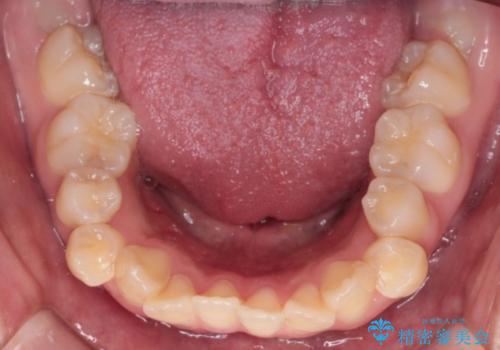

【インビザライン】シザーズバイト、抜歯矯正

- オープンバイトを主訴に来院された患者様です。

抜歯を行うことで、インビザラインを用いて前歯を下げることができ、同時にオープンバイトを改善することができました。

今回はインビザラインのみで治療を終了することができました。